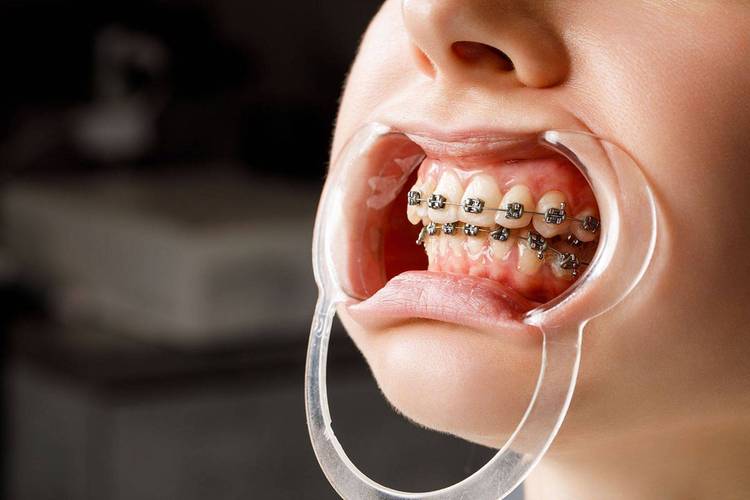

随着技术发展,牙齿矫正已从传统的“铁齿钢牙”演变为多种方式,每种方式的特点、价格、适合人群不同,需根据自身需求选择,以下为常见矫正方式的对比:

| 传统金属托槽 | 价格低、强度高、适用范围广(复杂畸形也可用) | 美观性差、易刮嘴、口腔异物感强 | 8000-15000 | 预算有限、牙齿畸形复杂者 | 1-2个月一次 |

| 陶瓷托槽 | 托槽与牙齿颜色相近,美观度高于金属托槽 | 硬度低于金属,易磨损、断裂,价格稍高 | 12000-20000 | 对美观有要求、预算中等者 | 1-2个月一次 |